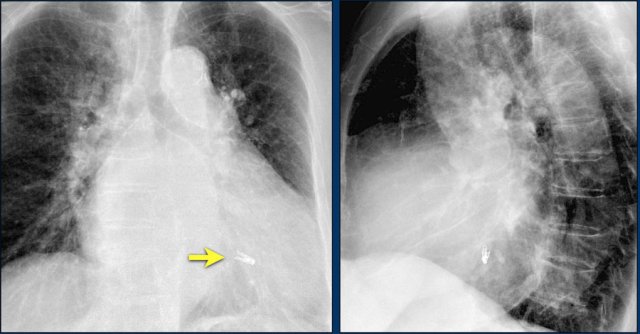

The image is taken immediately after placement of an ICD.

There is a small pneumothorax (arrow).

This is the most common complication.